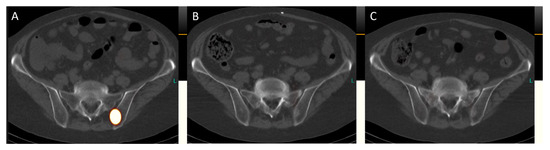

Figure 6. Transversal images of the post-therapeutic SPET/CT scans (Figure 6, (A), July 2023; (B), September 2023; (C), November 2023) reveal the complete remission of bone metastases. For instance, in the left ilium adjacent to the sacroiliac joint, a sclerosed lesion is now visible, indicating successful treatment.